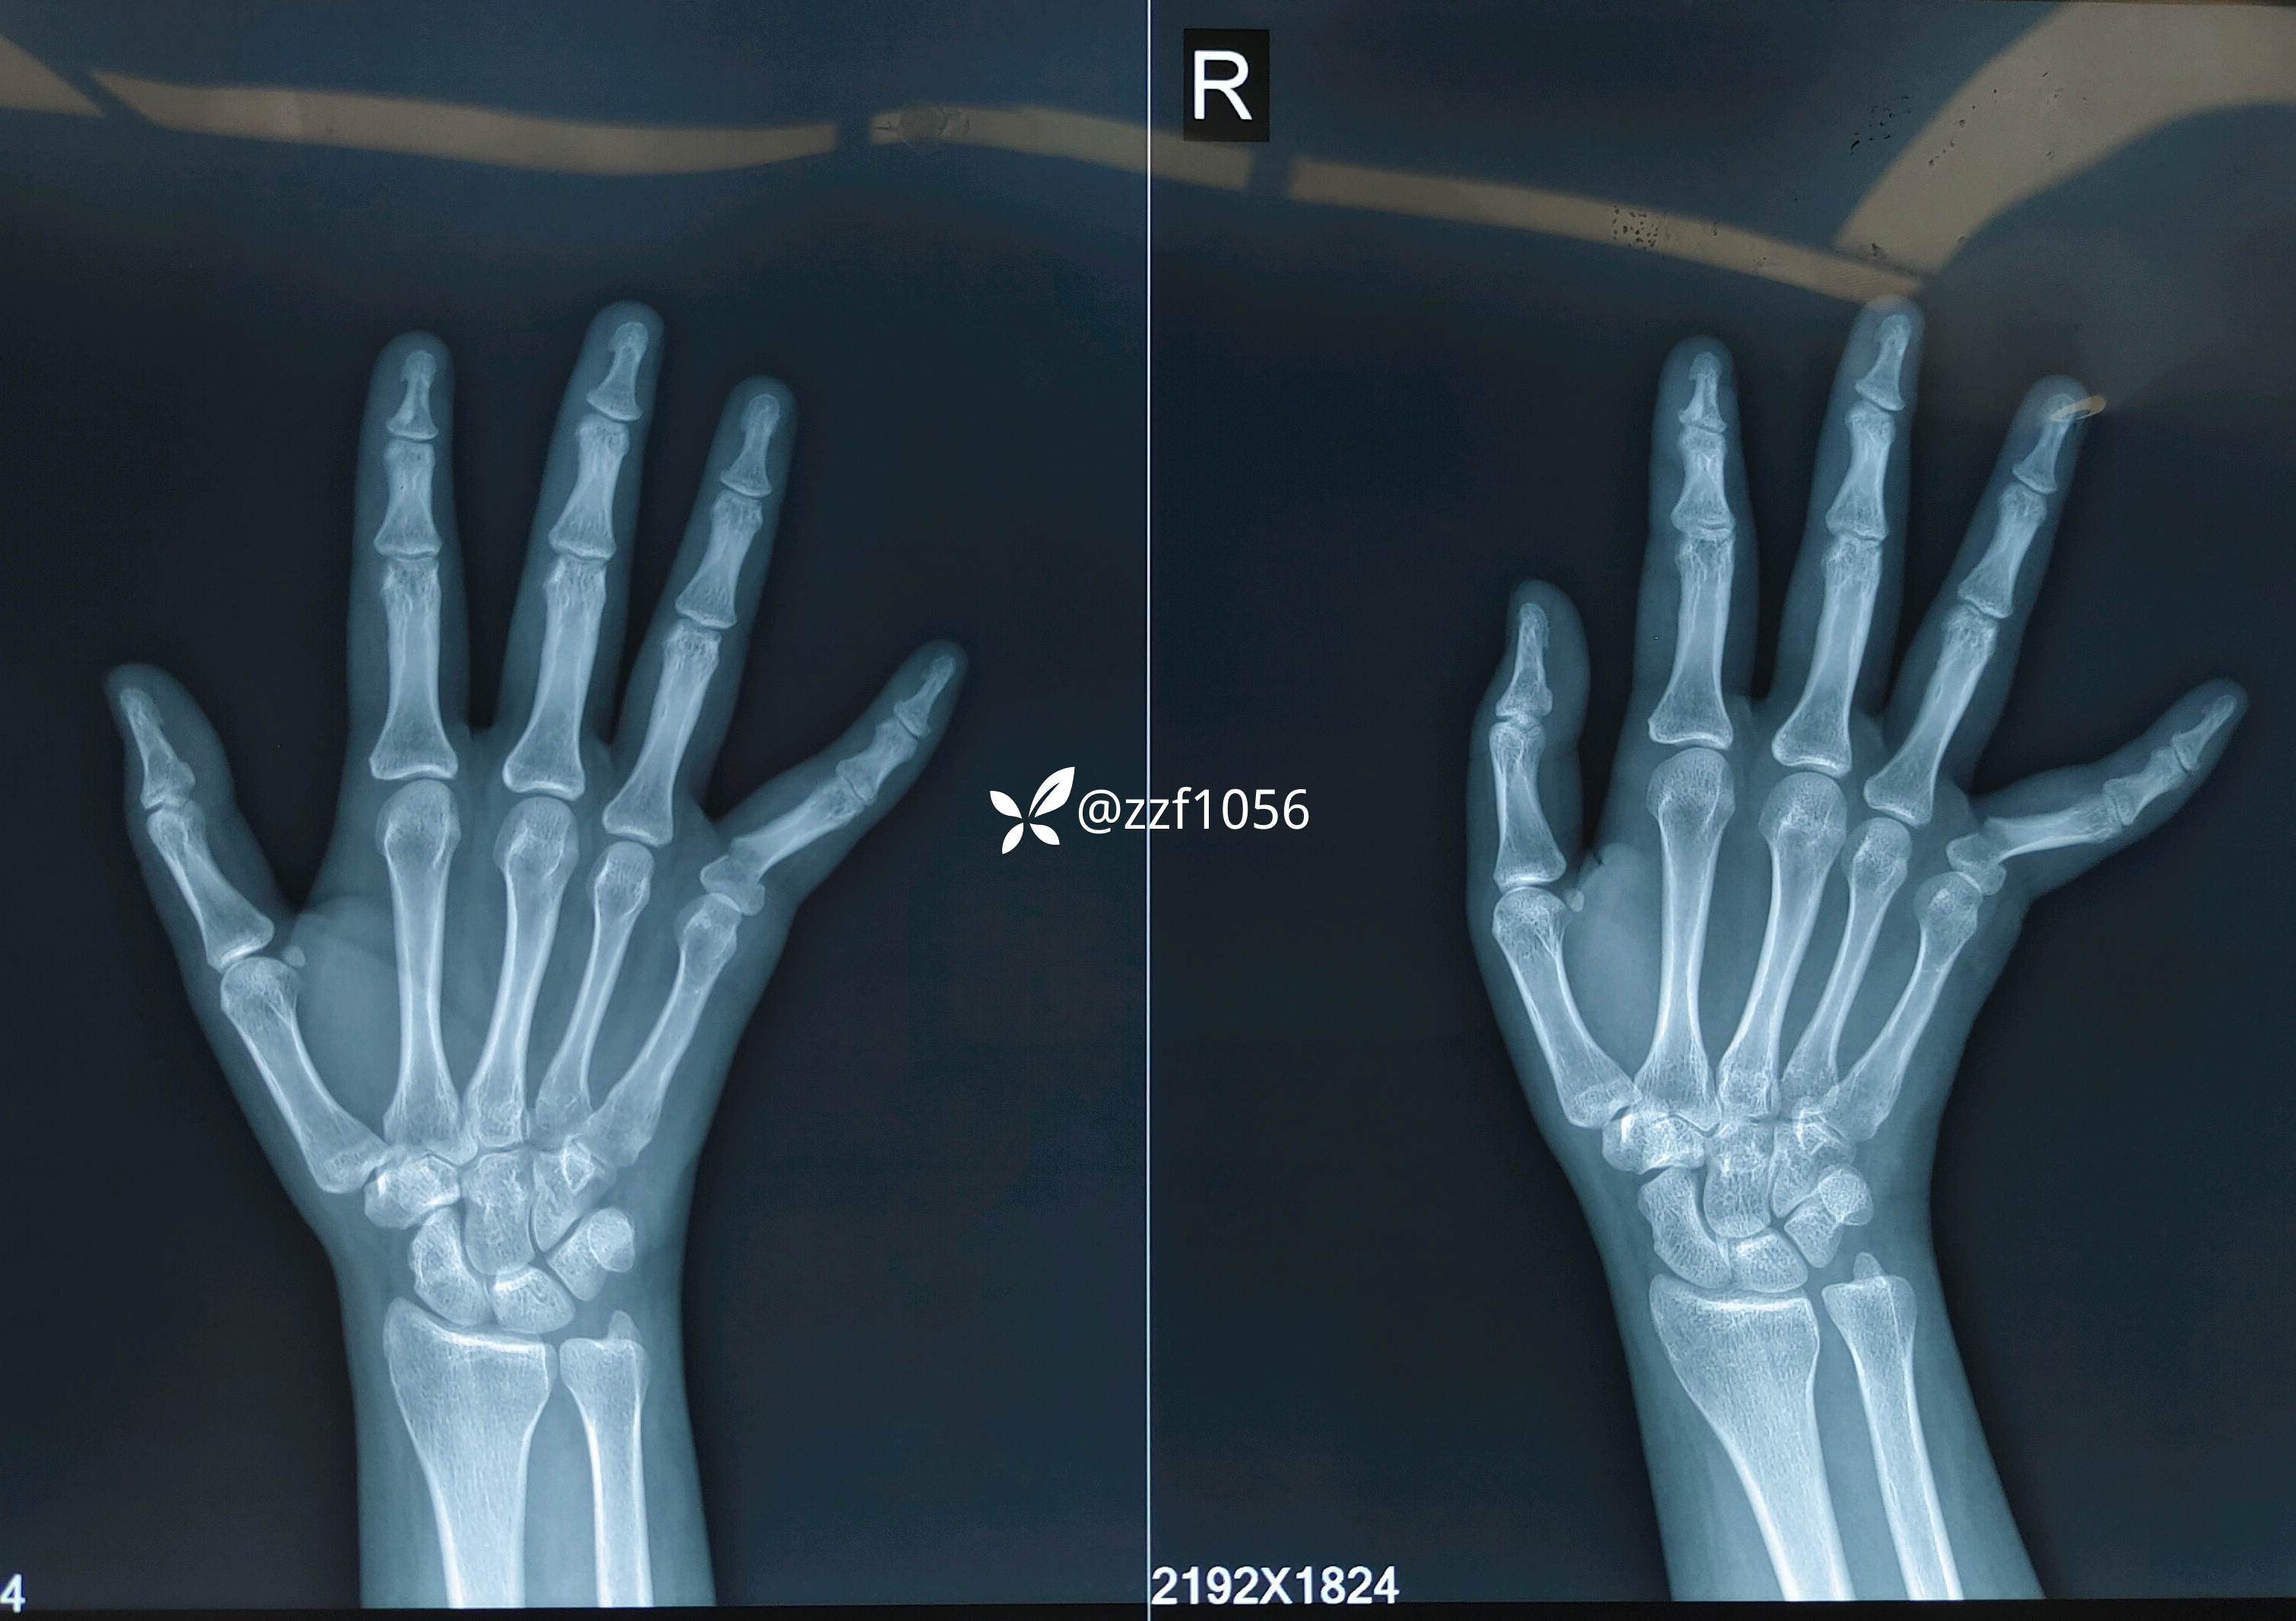

患者女,24岁,高中英语老师,右手小指外伤后肿痛、畸形18小时。

上午门诊,一女家属拿着手机找我看片,说她在外地当高中老师的妹妹昨天晚上骑车受伤了问我怎么治疗更好,手机微信图片显示右手小指近节基底骨折移位,我告知找当地医院手法整复石膏固定即可,家属说当地医院让开刀手术,知道你们医院微创做的好,现在正从200多公里的外地往这赶。

15:10分消毒铺巾准备台上行腕部神经阻滞麻醉,手法整复直接经皮交叉穿针,术中透视并调整,处理针尾,术中活动良好克氏针稳定;